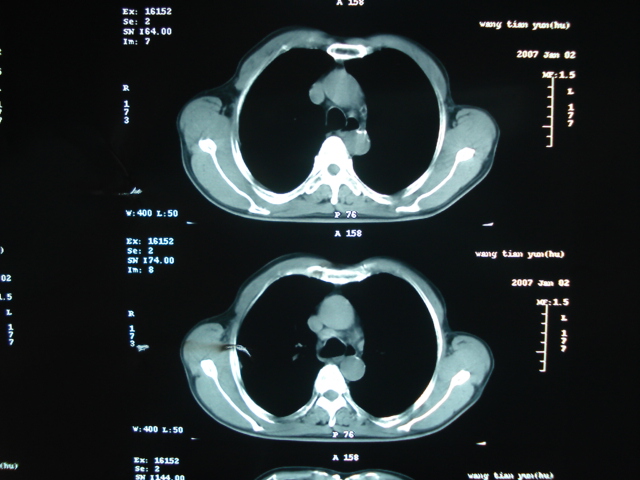

以下是引用狙击手在2007-4-18 20:17:00的发言:[br]原:2007/1/22号ct片:右肺上叶可见片状、云雾状高密度影,右肺上叶后段可见三角形高密度影,尖端指向肺门,右肺上叶后段支气管壁不规则增厚,管腔不规则增厚,纵隔未见肿大淋巴结.[br] 今ct:右肺上叶片状影增大,右肺上叶后段不张及右肺上叶后段支气管壁不规则增厚未见变化,右肺下叶背段支气管壁不规则增厚.[br] 如果考虑肺结核,但从临床证据看竟然没有一项支持肺结核,不知患者是否已经过正规抗结核治疗。没有的话,3个月了前后片看起来变化不大,似乎有不太符合肿瘤征象,不知患者是否抗炎治疗过,下叶支气管增粗还是要高度警惕,同意楼主意见,将常规病理,生化检查再做一遍。[br]

以下是引用狙击手在2007-4-18 20:17:00的发言:[br]原:2007/1/22号ct片:右肺上叶可见片状、云雾状高密度影,右肺上叶后段可见三角形高密度影,尖端指向肺门,右肺上叶后段支气管壁不规则增厚,管腔不规则增厚,纵隔未见肿大淋巴结.[br] 今ct:右肺上叶片状影增大,右肺上叶后段不张及右肺上叶后段支气管壁不规则增厚未见变化,右肺下叶背段支气管壁不规则增厚.[br] 如果考虑肺结核,但从临床证据看竟然没有一项支持肺结核,不知患者是否已经过正规抗结核治疗。没有的话,3个月了前后片看起来变化不大,似乎有不太符合肿瘤征象,不知患者是否抗炎治疗过,下叶支气管增粗还是要高度警惕,同意楼主意见,将常规病理,生化检查在做一遍。[br]